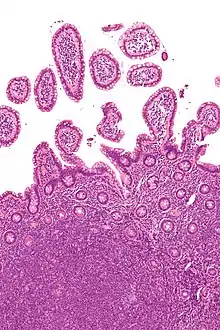

| Micrograph showing mantle cell lymphoma (bottom of image) in a biopsy of the terminal ileum. H&E stain. | |